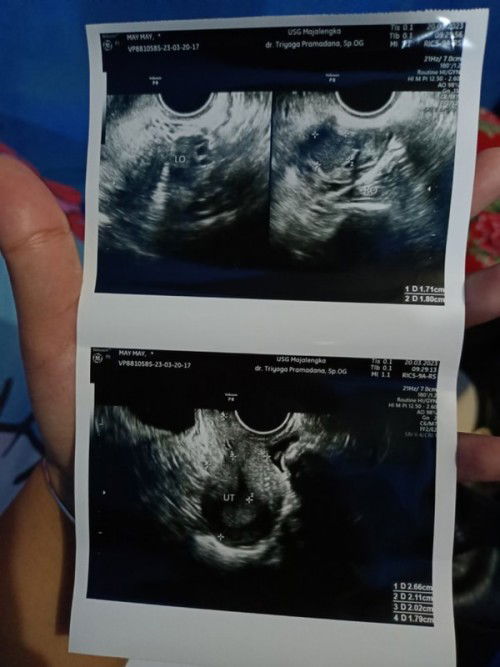

Bunda maaf saya mau tanya, waktu tgl 20 kemarin saya usg transvaginal hasil menurut dokter rahim saya bagus ada kista kecil tapi itu tidak bermasalah katanya. Saya mau tanya itu yang ada tulisan dari 1 D sampai 4 D itu ukuran sel telurnya atau gimna ya?soalnya saya lupa tanya tentang itu sama dokternya#bantusharing #ingintahu #pejuanggaris2 #pleasehelp #seriusnanya